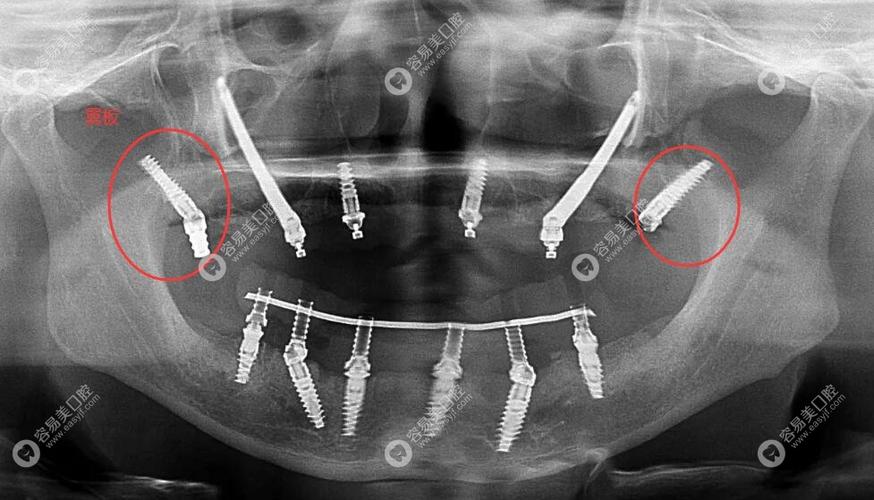

颧骨植牙的技术原理是通过外科手术,将特制的长种植体(长度通常可达30-55mm)从口腔前庭切口进入,穿过上颌骨,最终植入颧骨主体内,种植体的头部(基台)仍位于牙槽嵴顶,用于连接牙冠,而尾部则固定在颧骨内,通过颧骨的支撑力分散咀嚼力,从而恢复牙齿功能,这种种植方式也被称为“颧骨支抗种植”,其核心优势在于无需依赖上颌后牙区的牙槽骨,避免了复杂的骨增量手术(如骨移植、上颌窦提升等)。

术前需进行详细的影像学检查,如锥形束CT(CBCT)和三维重建,明确颧骨的骨量、密度、解剖结构(如颧牙槽嵴、上颌窦位置),以及周围重要神经血管(如眶下神经、上颌动脉)的走行,结合口腔模型和咬合关系,设计种植体的植入位置、角度和长度,确保种植体能获得初期稳定性,且不影响后期修复体的美观与功能。

通过专用种植机,将特制的长种植体(表面通常采用钛或钛合金涂层,以促进骨结合)从上颌骨前壁穿入,沿着预设的角度和深度,植入颧骨主体内,术中需实时监测种植体的位置,避免损伤上颌窦或周围神经血管,植入后,通过扭矩测试确认种植体的初期稳定性(通常要求植入扭矩超过35N·cm)。